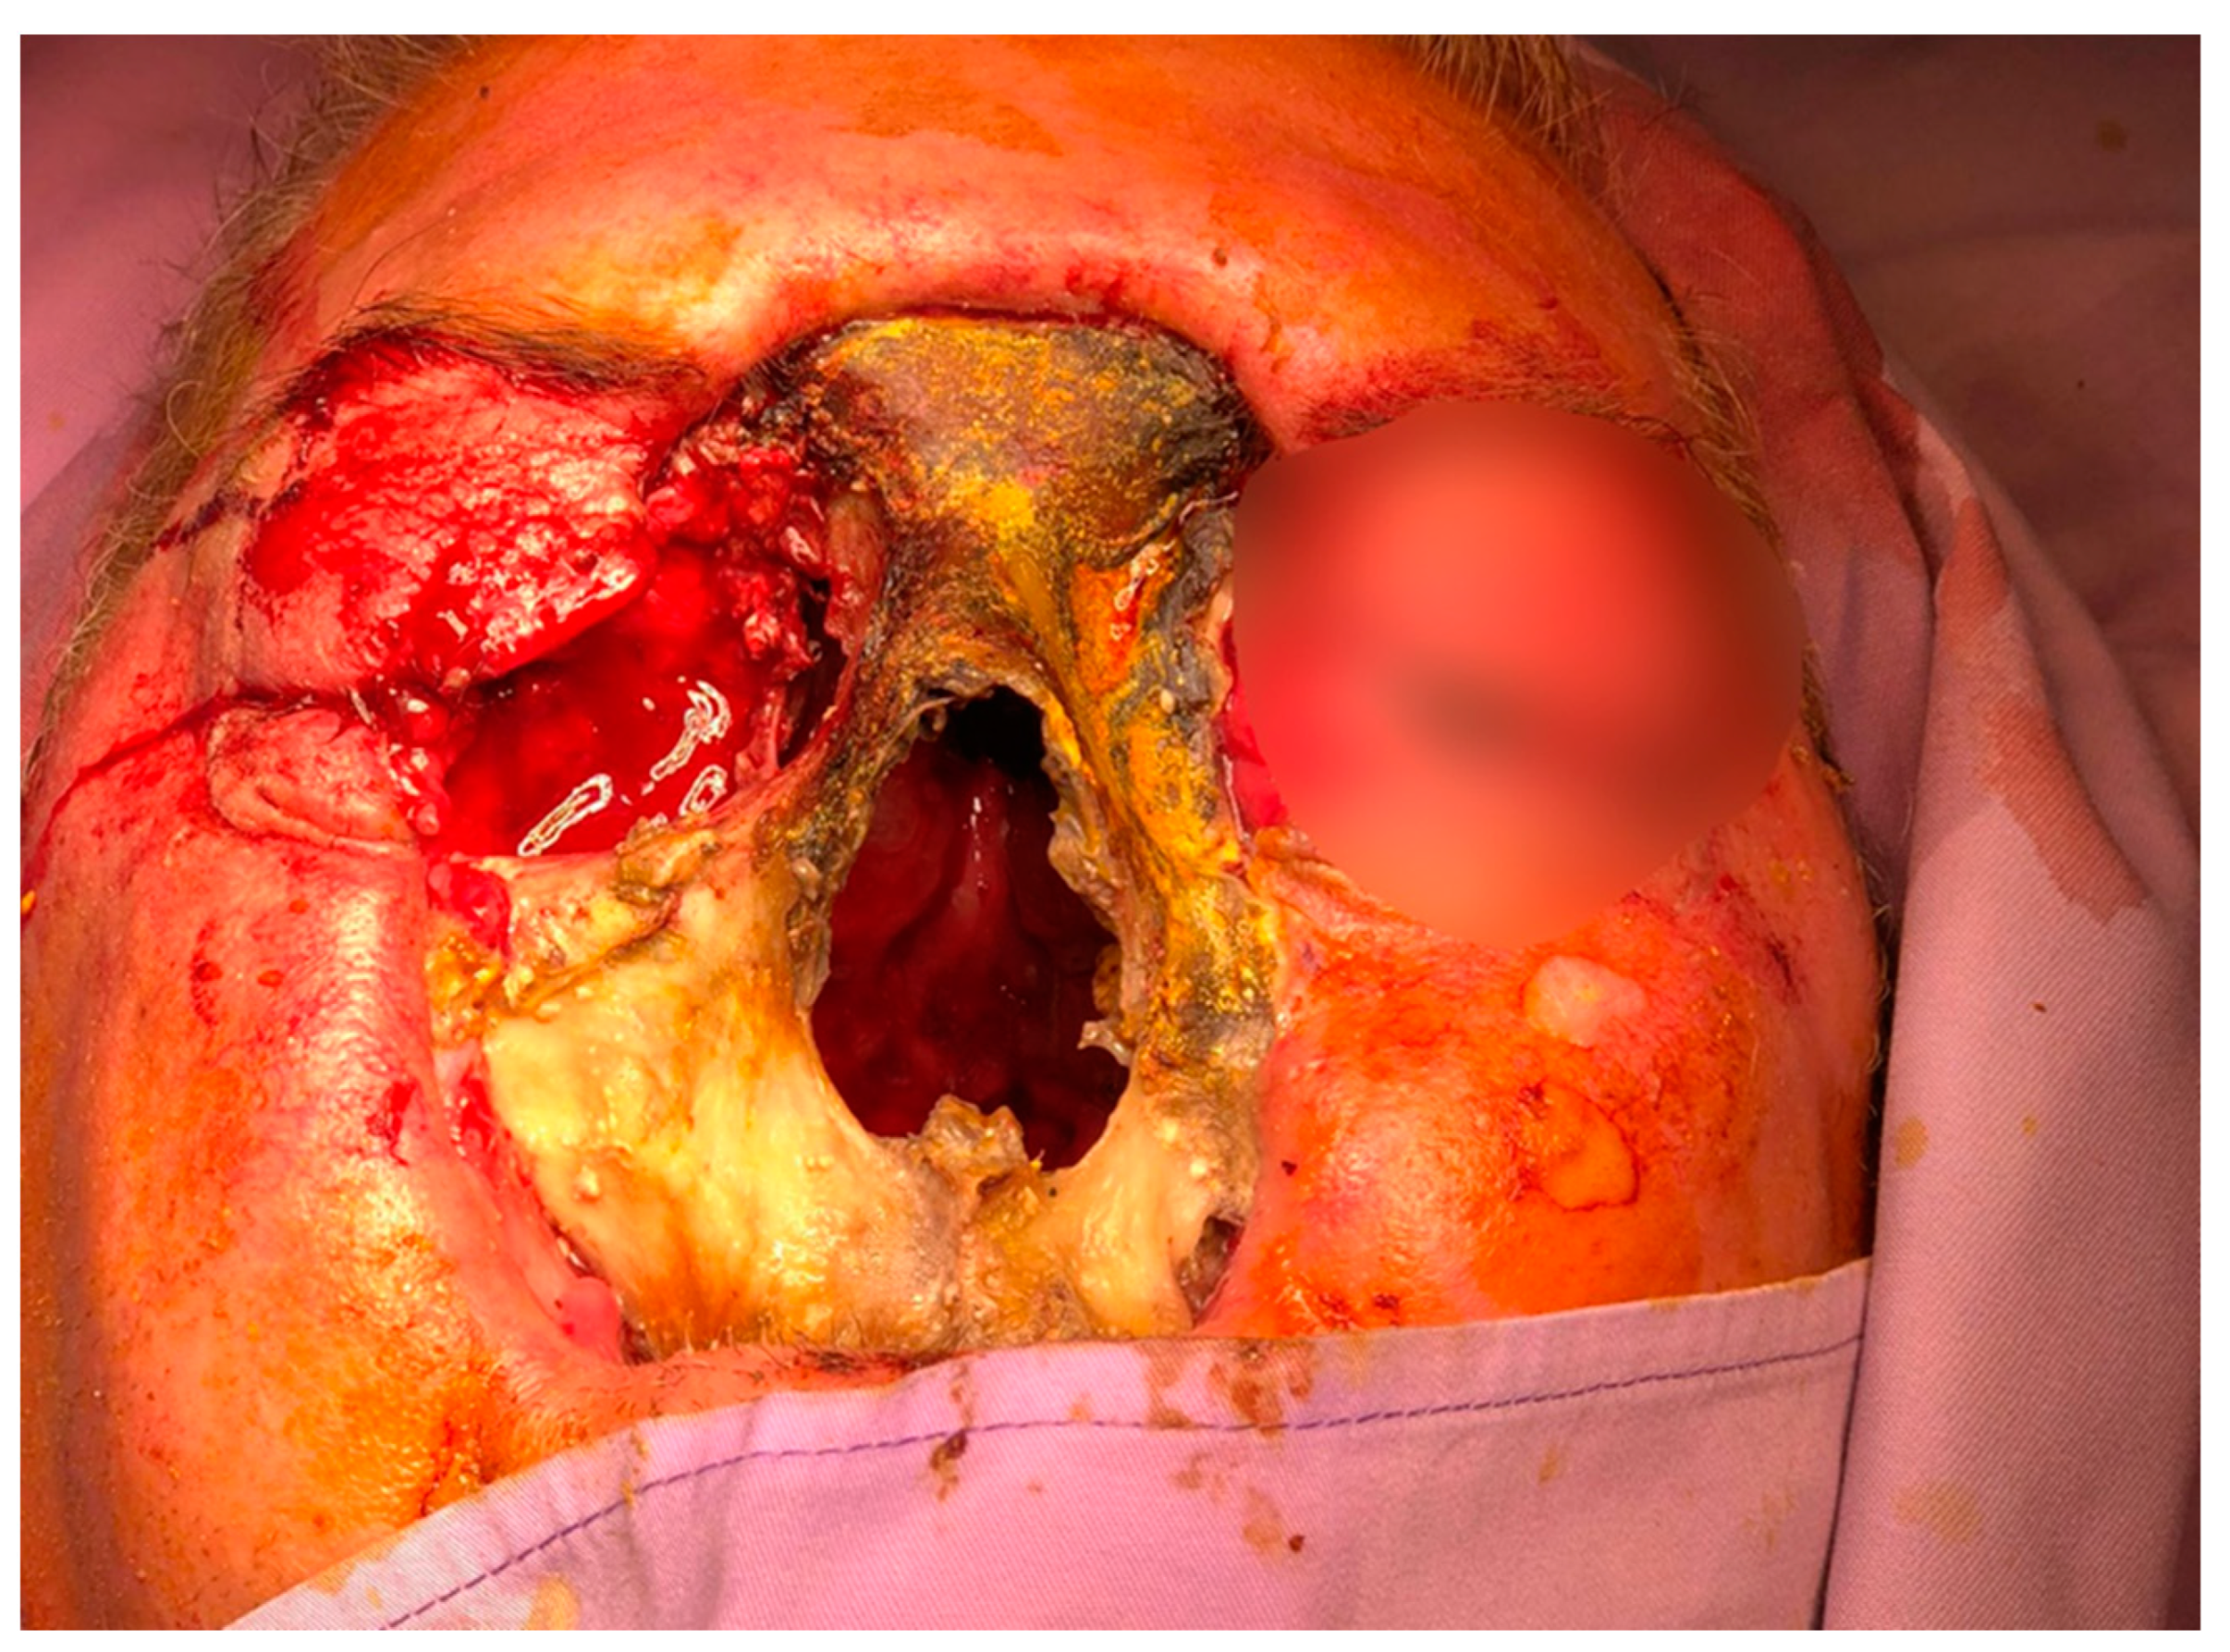

Subsequently, on 30 August 2022, he developed edema in the upper and lower eyelids, diffuse facial edema with Celsian signs, and associated centrofacial vascular necrosis at the level of the nasal pyramid with right orbital extension and the involvement of the right maxillary sinus, accompanied by headache, leading to admission to the Ear Nose Throat (ENT) department, Figure 2. A macroscopic anatomopathological examination revealed multiple necrotic fragments and a microscopic examination showed multiple histological sections represented by necrotic-inflammatory material, with numerous bacterial colonies and fungal filaments, and some branching at a 90-degree angle, consistent with mucormycosis, Figure 3. Cranial CT showed massive destructive infectious processes involving the maxillary sinuses, posterior ethmoid cells, and orbits with involvement of the right eye globes, possibly of mixed fungal and bacterial etiology, Figure 4. Surgical treatment was instituted by performing a total necrectomy of the centrofacial necrotic focus along with antibiotics (amoxicillin-sulbactam, cefoperazone) for 10 days and antifungal therapy with posaconazole (for 9 weeks) due to myelosuppression. Amphotericin B and isavuconazole were not available at that time in the hospital. Postoperative recovery was satisfactory, and subsequently, he was transferred to the hematology service for further specialized treatment.

Figure 2. The clinical aspect of the patient. Edema in the upper and lower eyelids with diffuse facial edema and centrofacial vascular necrosis at the level of the nasal pyramid with right orbital extension and involvement of the right maxillary sinus.